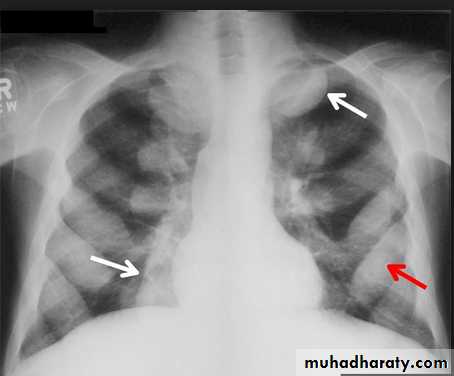

Tension pneumothorax.

On a posteroanterior chest x-ray (A), the left hemithorax is very dark or lucent because the left lung has collapsed completely (white arrows).

The tension pneumothorax can be identified because the mediastinal contents, including the heart, are shifted toward the right, and the left hemidiaphragm is flattened and depressed. A computed tomography scan done on a different patient with a tension pneumothorax (B) shows a completely collapsed right lung (arrows) and shift of the mediastinal contents to the left.

chest practice

Tension Pneumothorax. Portable chest film in a 43-year-old woman with ARDS shows a large right pneumothorax with mediastinal shift and ipsilateral diaphragmatic depression, suggesting tension.

Air was evacuated under pressure during emergent placement of a right chest tube.